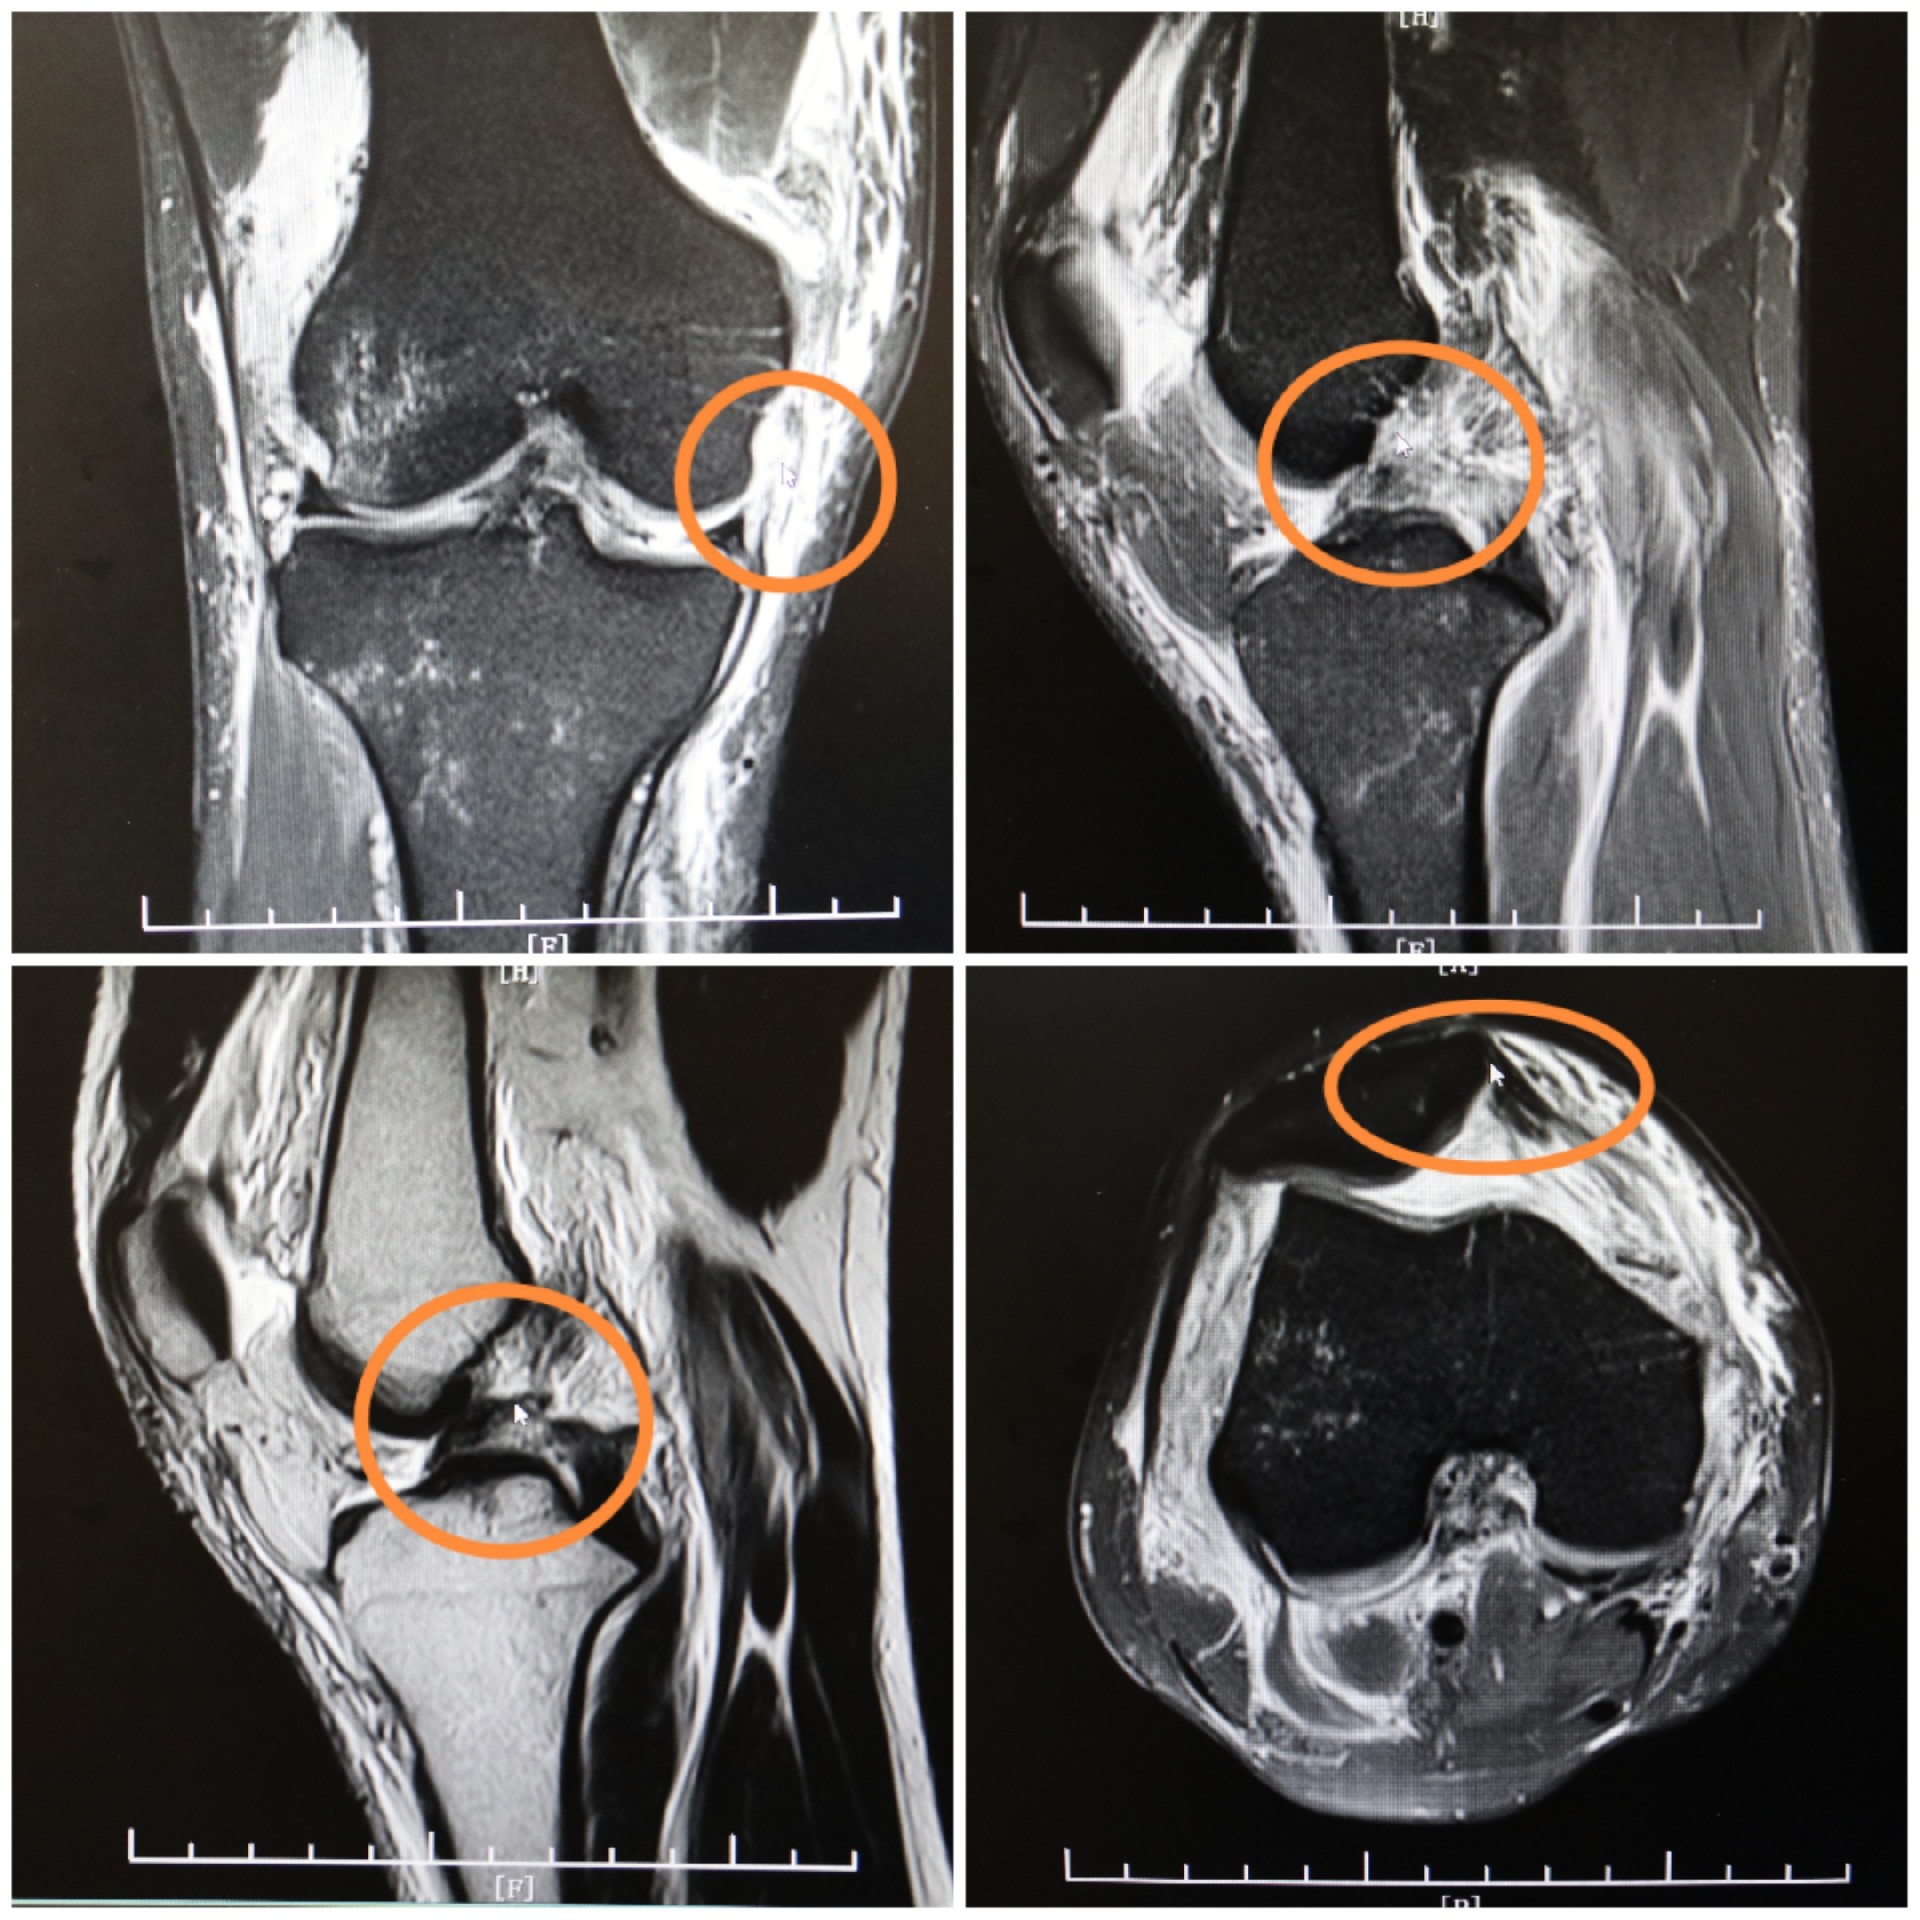

周武忠主任检查发现患者压痛明显,关节活动受限,行走困难。经影像检查诊断王先生右侧膝关节前交叉韧带撕裂内侧副韧带撕裂后交叉韧带撕裂外侧半月板撕裂,伤情比较严重,保守治疗对预后效果不佳。